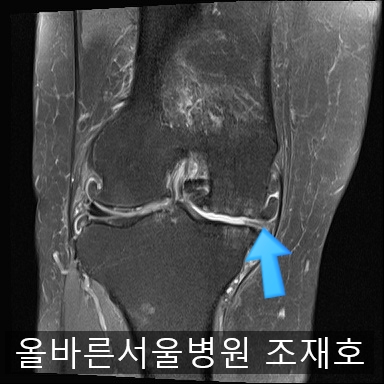

为了掌握具体情况拍了MRI。

image_2475163911519368491057.jpg

内侧关节软骨几乎不见,软骨板也受损严重。软骨损伤部位充满关节液。

虽然前方十字韧带粘液样变性,但稳定性无异常